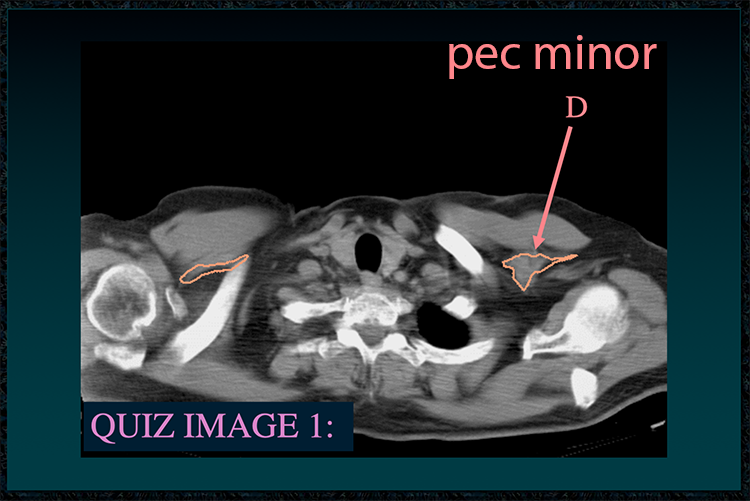

◂Chest Anatomy Review